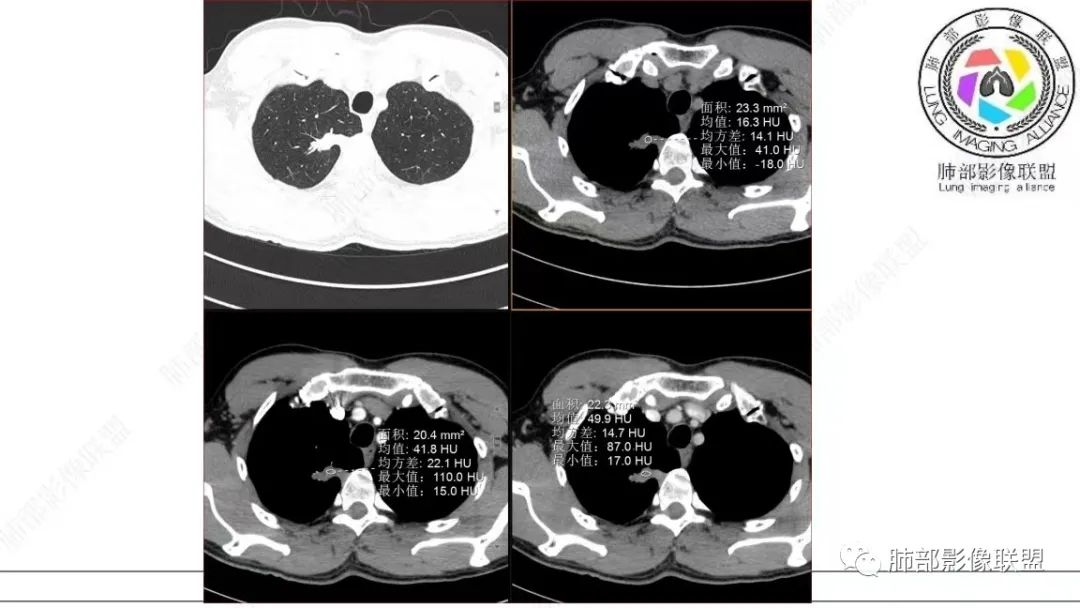

仔细看,里面是有低密度的。平扫CT值也很低,才16HU。

增强也很有特点。这些低密度,是有延迟强化特点的。

平扫低密度,就这个病变而言,我们最容易想到的:干酪性坏死、黏液。而延迟强化。所以这个病变是不符合干酪性坏死的表现的。很多平直凹陷的地方,与胸膜宽基底接触,是否存在胸膜牵拉不详,需重建看看。说明这个病变是有收缩力的。里面含有一部分纤维。当然,含有纤维的,肿瘤的肌成纤维可以,上皮间质转换可以,慢性炎也可以,好多病变里面可以有纤维。干酪样坏死,是不会强化的。延迟强化,肉芽肿可以,纤维比较多的或者黏液多的也可以。